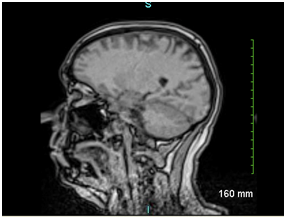

Because branch retinal artery occlusion could not be ruled out, the patient was admitted for the following lab work: complete blood count, Hemoglobin A1C, ANA, lipid panel, RPR/FTA-ABS, HIV, PT/PTT. Imaging was also obtained which included CT (Figure 1) and MRI (Figure 2) as well as echocardiogram of the heart. No imaging abnormalities were found, and there were no abnormal labs besides the positive RPR, including a non-reactive HIV test. When the patient was notified of his positive RPR titer (1:64) with confirmatory FTA-ABS, he returned to the hospital for lumbar puncture which did not reveal any treponemal organisms in his CSF. The patient was initiated on a 14-day course of IV Penicillin, which he completed without complication. The patient’s vision changes have since resolved with no permanent damage noted on funduscopic exam.

Figure 1 CT head with contrast.